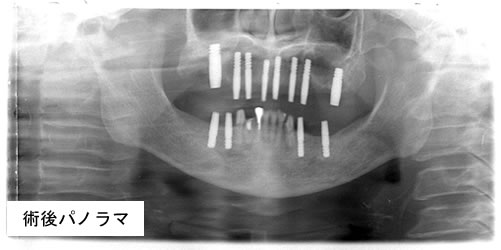

2013.11.19(火)

「下顎無歯顎症例に即時荷重

インプラント手術を行いました」

‘上顎臼歯部2本 下顎14本 計16本欠損 69歳 男性’

~ 上下合計10本インプラントを植立 ~

その日のうちに仮歯を入れ, 噛めるようにしました。